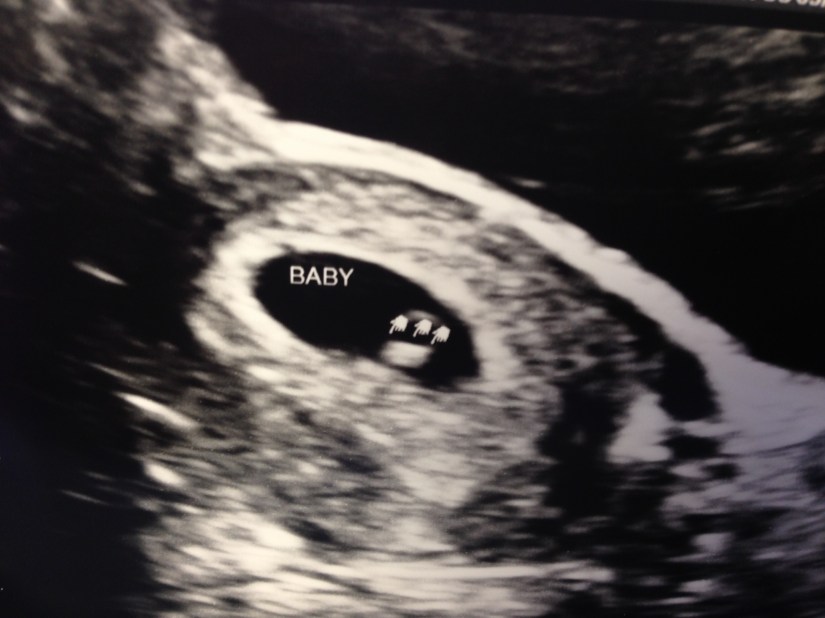

Since I couldn’t post any baby related pictures over the last 13 weeks I’ve posted some below to help catch you up. Over the next few months I’ll try to keep you guys updated on the highs and lows of pregnancy so stay tuned!